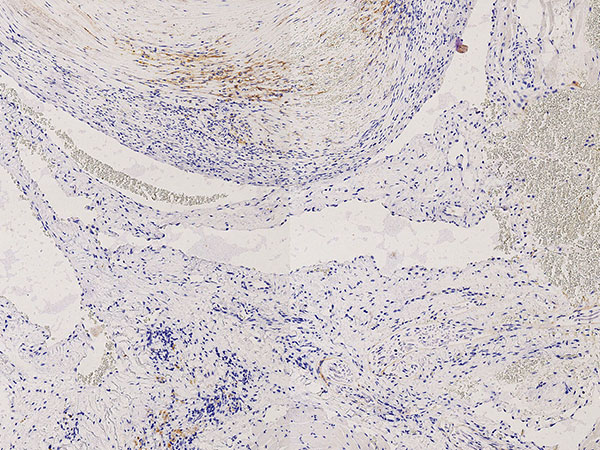

Histopathologie, CD31-Färbung, 110-fache Vergrößerung: Die starke Anfärbung (dunkelbraun gefärbte Endothelzellen) mit dem gefäßendothel-spezifischen Marker CD-31 der gesamten Begrenzung der irregulären, gefäßartigen dysplastischen Hohlraumstruktur weisst klar auf eine Gefäßmalformation hin. Unter dem Gefäßendothel ist nur eine sehr dünne Gefäßwandung nachweisbar.